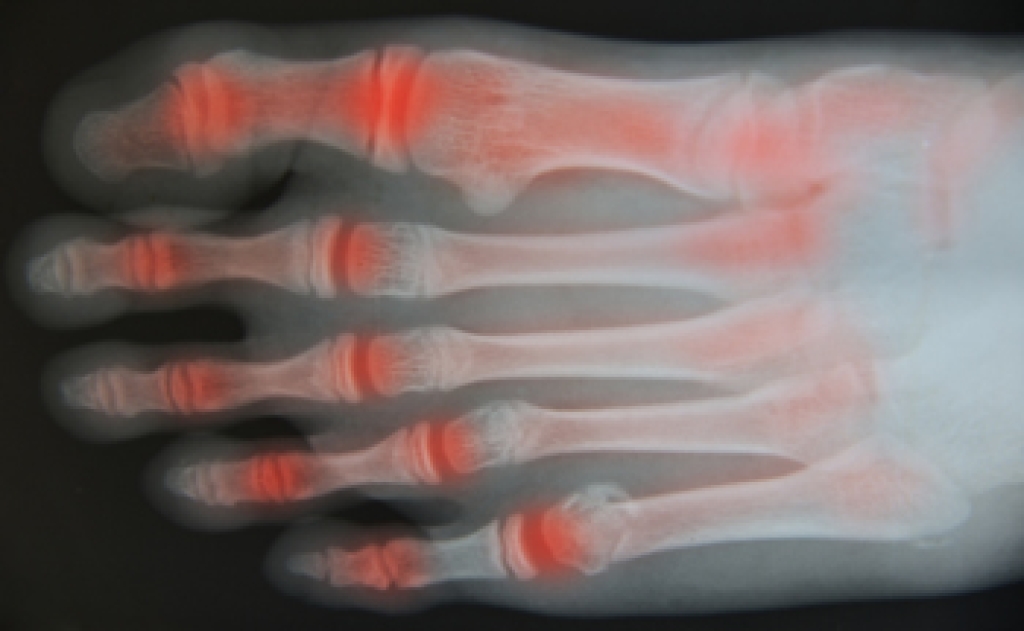

Psoriatic arthritis is an inflammatory condition linked to psoriasis that often affects the feet and toes. It can develop when the immune system mistakenly attacks healthy joints and tissues. Common causes include genetic factors and immune system dysfunction. Symptoms in the feet may include joint pain, swelling, stiffness, and changes in toenails, such as pitting or separation from the nail bed. The inflammation can make walking difficult and painful. A podiatrist can help by evaluating joint function, managing inflammation, recommending supportive footwear or orthotics, and coordinating care with other specialists. If you experience persistent foot pain with a history of psoriasis, it is suggested that you are under the care of a podiatrist to receive expert care, while improving your mobility.

Arthritis is a term that is commonly used to describe joint pain. The condition itself can occur to anyone of any age, race, or gender, and there are over 100 types of it. Nevertheless, arthritis is more commonly found in women compared to men, and it is also more prevalent in those who are overweight. The causes of arthritis vary depending on which type of arthritis you have. Osteoarthritis for example, is often caused by injury, while rheumatoid arthritis is caused by a misdirected immune system.

Arthritic symptoms range in severity, and they may come and go. Some symptoms stay the same for several years but could potentially get worse with time. Severe cases of arthritis can prevent its sufferers from performing daily activities and make walking difficult.